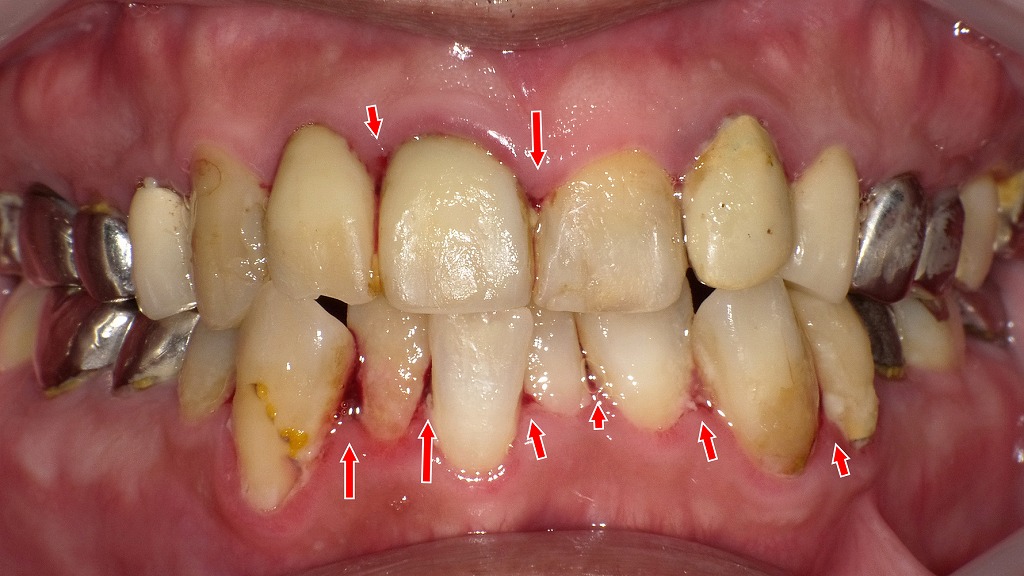

「血が出ても構わず磨けば治る」と思い込んで、強くブラッシングを続ける方が少なくありません。しかしこれは大きな誤解です。

出血は歯茎の炎症サインであり、歯周病が進行している可能性を示しています。無理にゴシゴシ磨き続けることで、炎症が治まるどころか歯茎がさらに傷つき、歯肉退縮(歯茎が下がる)や知覚過敏の悪化を招くこともあります。

また、傷ついた歯肉から細菌が血管に入り込むことで歯原性菌血症のリスクも上がり、全身疾患につながる恐れもあります。